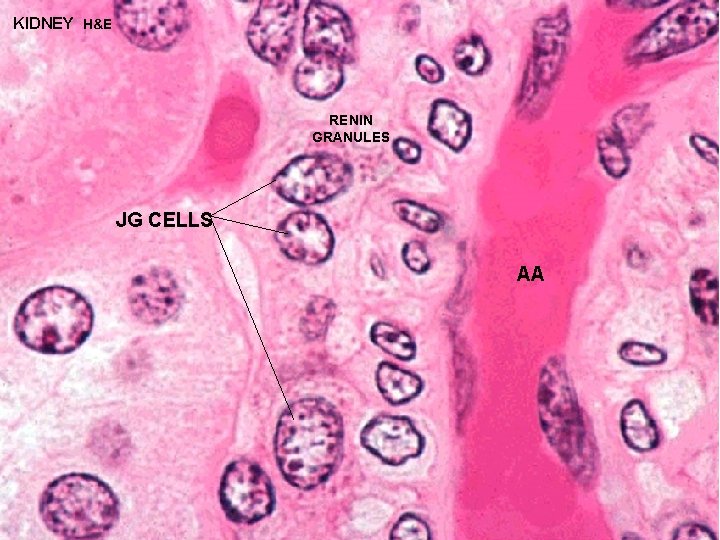

URINARY SYSTEM JUXTAGLOMERULAR MACULA DENSA + JUXTAGLOMERULAR (JG) APPARATUS CELLS REGULATE BLOOD FLOW THROUGH GLOMERULUS MACULA DENSA - cells located in the DCT in close contact with the glomerulus and the afferent and efferent arterioles JG CELLS - specialized smooth muscle cells in the wall of the afferent arteriole which contain and secrete RENIN to regulate blood flow through the glomerulus ANGIOTENSINGO GEN (PLASMA PROTEIN) RENIN ANGIOTENSIN II ALDOSTERONE SECRETION VASOCONSTR

KIDNEY H&E RENIN GRANULES JG CELLS AA